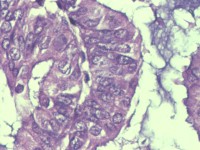

性别

女

年龄

55岁

临床诊断

异常子宫出血

一般病史

阴道不规则出血1月

标本名称

子宫内膜

大体所见

灰白色组织1堆、4*3.4*2.2CM大。

能诊断癌吗

子宫内膜样腺癌